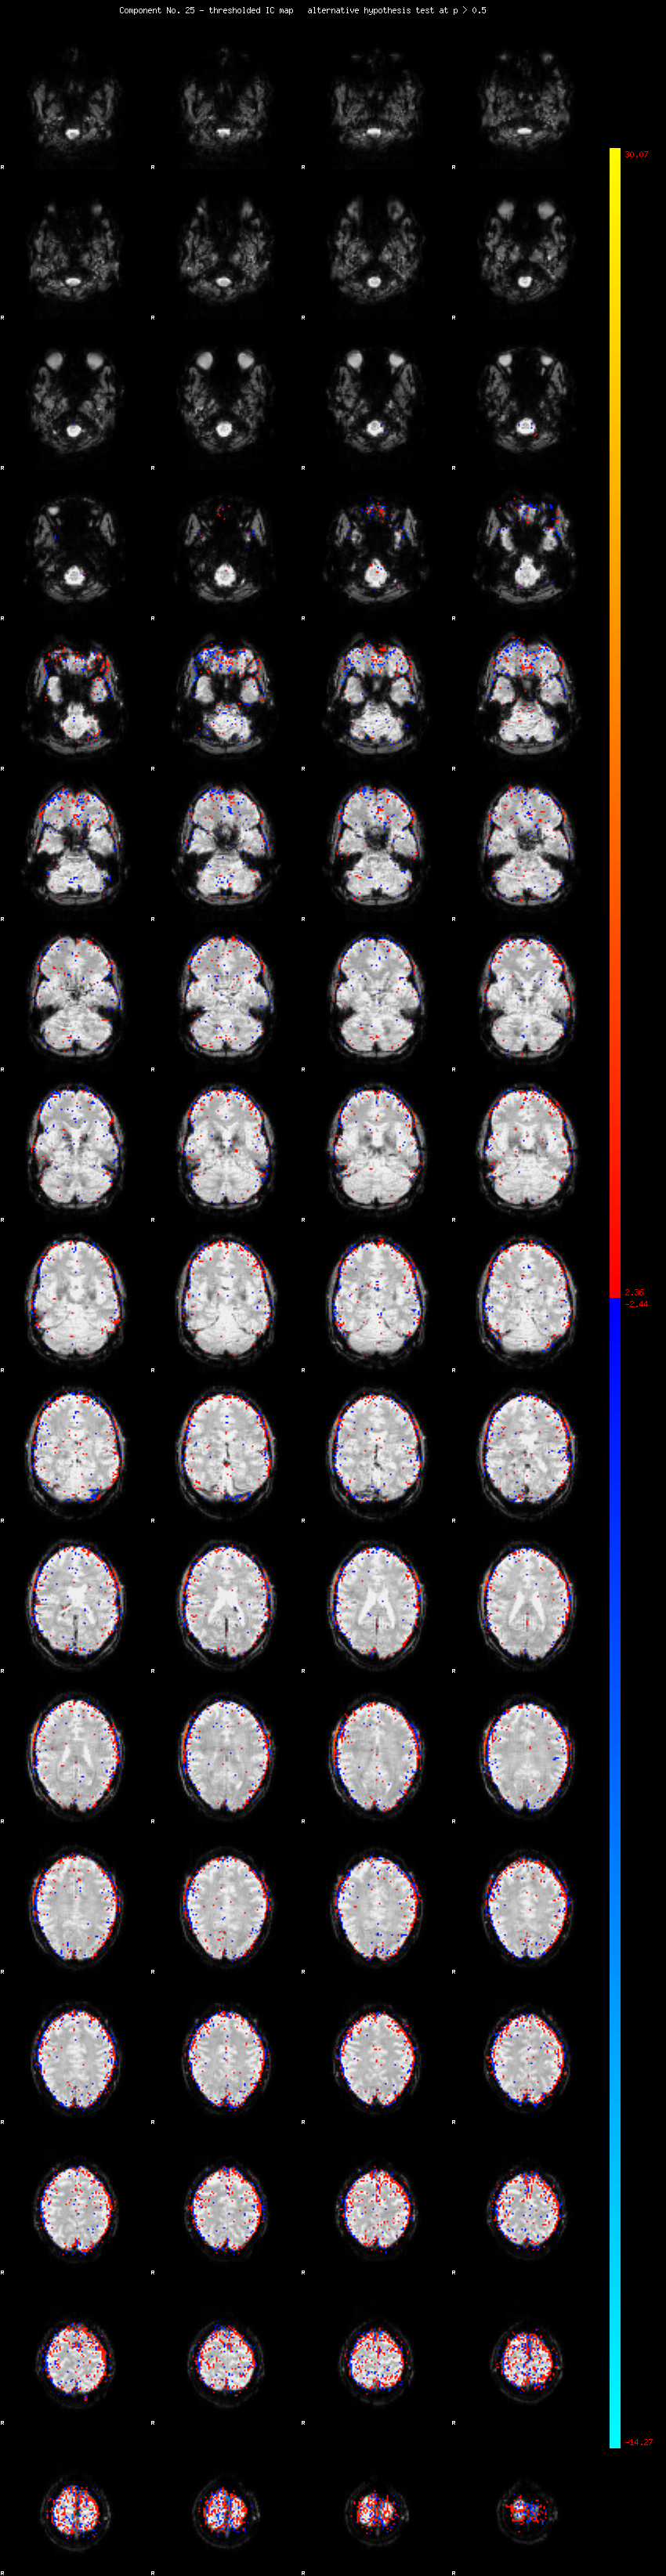

MELODIC Component 25

1.26 % of explained variance;     0.84 % of total variance

MMfit